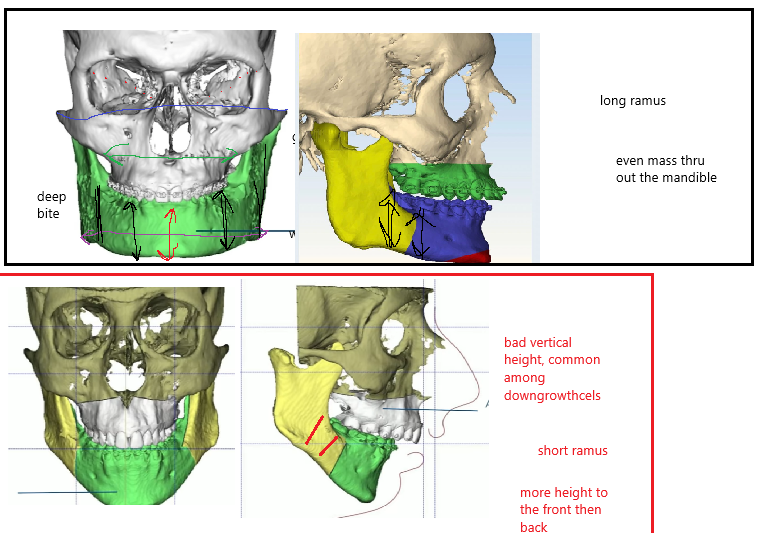

2. Good vertical height across the whole mandible(long ramus big part of it), but if you got too much you will be ogre( very bad). black box is good, red bad:

Lets now look at another alfaro case which didnt have equally good ascension, but he still had a sfs.

As we can see from the front he didnt have as much of a overbite or retrusion.

Because he didnt have much recession the lower jaw didnt became more vertically long as it wasnt hidden away behind a huge overbite or deep bite as in gustavos case. But he did a vertical genio which i think was a mistake

lets look at his bones and compare to gustavos:

2. Good vertical height across the whole mandible(long ramus big part of it), but if you got too much you will be ogre( very bad). black box is good, red bad:

Lets now look at another alfaro case which didnt have equally good ascension, but he still had a sfs.

As we can see from the front he didnt have as much of a overbite or retrusion.

Because he didnt have much recession the lower jaw didnt became more vertically long as it wasnt hidden away behind a huge overbite or deep bite as in gustavos case. But he did a vertical genio which i think was a mistake

lets look at his bones and compare to gustavos: